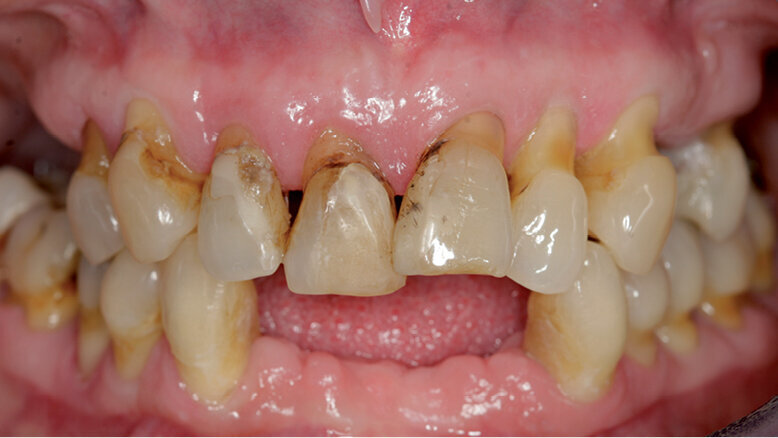

53letá pacientka se dostavila do naší praxe s dotazem, zda v jejím případě existují nějaké možnosti fixní zubní náhrady. Její dosavadní lékařka jí oznámila, že všechny zbývající zuby se musí kvůli špatnému stavu parodontu extrahovat (obr. 1). Zubní lékařka již vyrobila horní a dolní celkovou protézu jako imediátní náhradu. V rámci akutního zubního ošetření musely být při první konzultaci v naší praxi extrahovány čtyři dolní řezáky kvůli silnému stupni viklavosti (obr. 2) a nasazena imediátní náhrada těchto zubů.